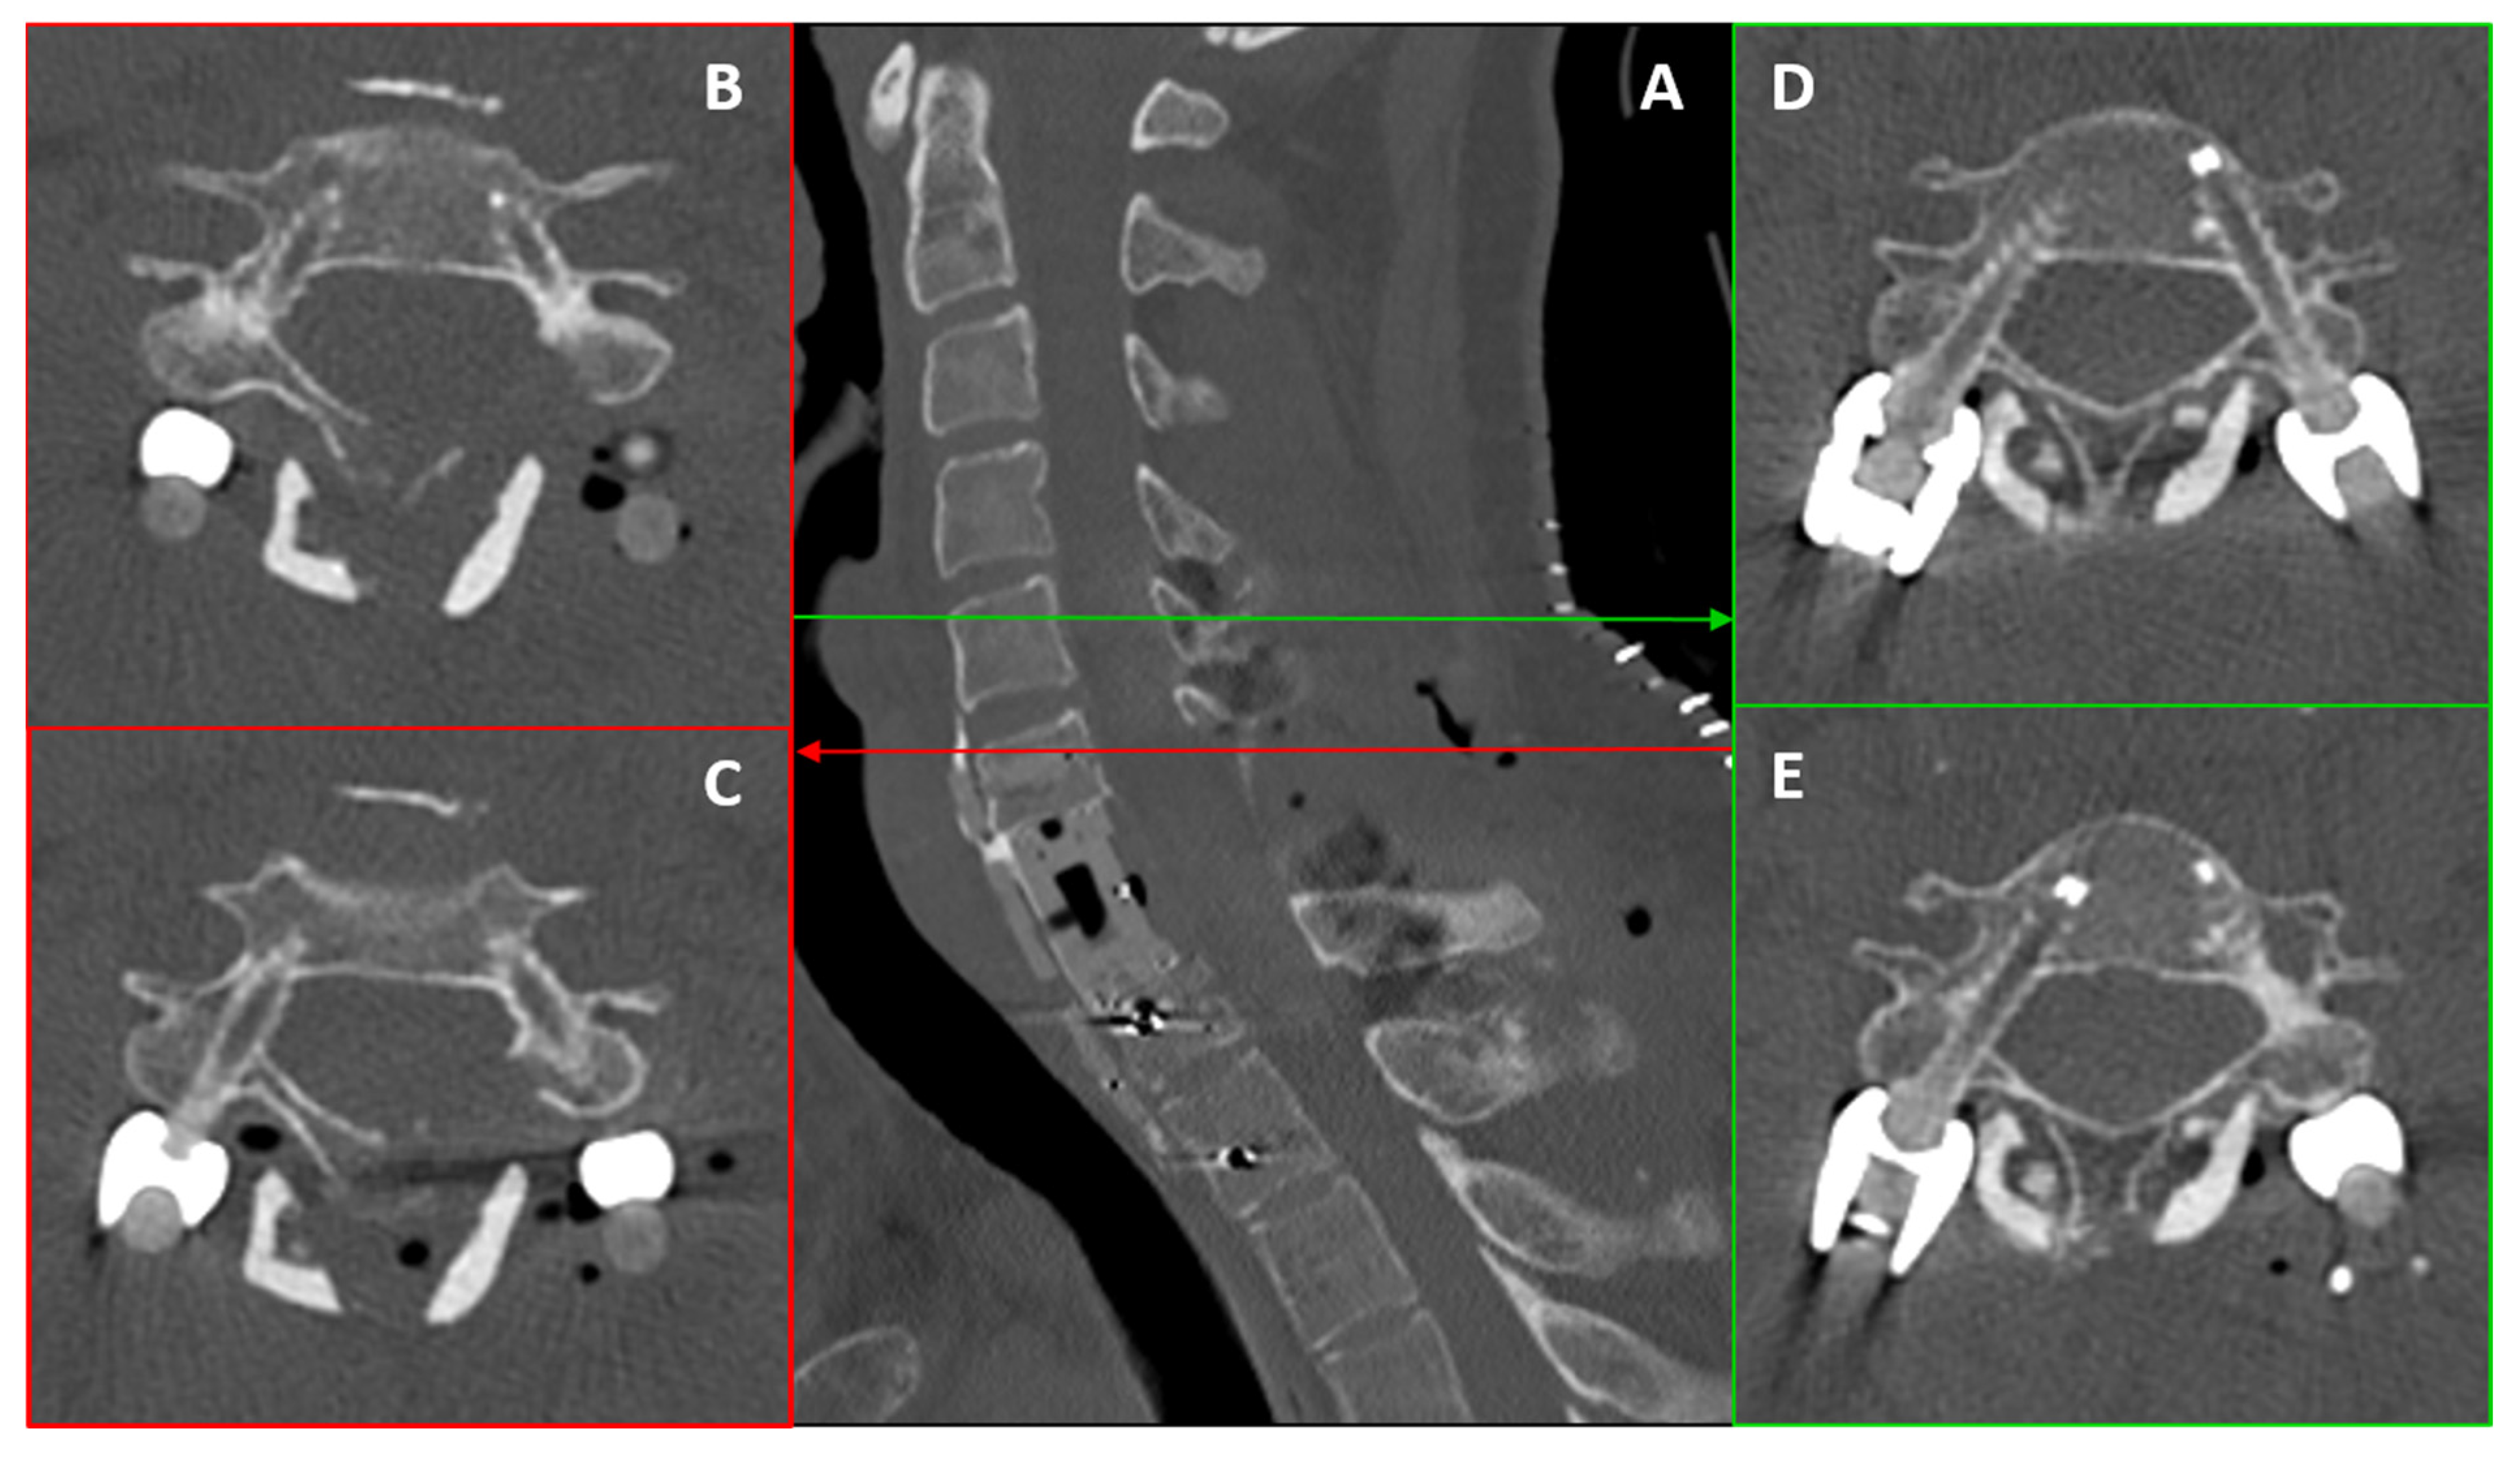

3.2. Posterior Step: Robot-Assisted Instrumentation

- Left Side (Repaired VA): The larger pedicle diameter allowed for a standard transpedicular trajectory.

- Right Side (Intact VA): Given the small pedicle diameter and the need to minimize lateral breach (risking injury to the only patent VA), we planned a small, controlled medial cortical violation, with limited encroachment into the canal, facilitated by robotic navigation. This choice is consistent with anatomical/clinical observations indicating higher vertebral artery risk with lateral breaches and short-term tolerance of limited medial violations [20,21,22].

| Level | Side | Pedicle Width (mm) | Screw Diameter (mm) | Mismatch (mm) |

|---|---|---|---|---|

| C5 | Right | 3.2–3.7 | 4.5 | +0.8–1.3 |

| C5 | Left | 3.7–4.0 | 4.5 | +0.5–0.8 |

| C6 | Right | 3.2–3.7 | 4.5 | +0.8–1.3 |

| C6 | Left | 3.7–4.0 | 4.5 | +0.5–0.8 |